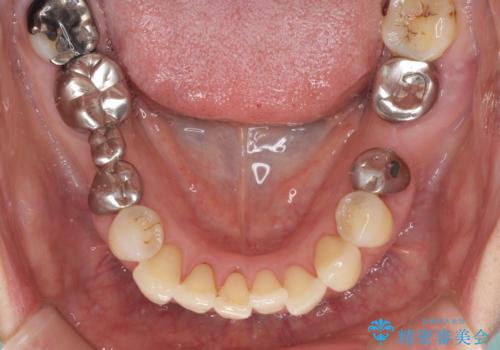

- 前歯の歯肉の腫れを気にして来院された患者様です。

前歯のみならず、奥歯の銀歯や下顎前歯のデコボコなど、色々と気になる部分を治したいとのことでした。

前歯は抜歯が必要であったので、抜歯を行い、その後歯肉移植をおこなった上でオールセラミックブリッジによる補綴治療を行うこととしました。

下顎と上顎臼歯部については矯正治療を行い、奥歯の欠損部位はオールセラミックブリッジを、その他の銀歯はセラミックインレーなどにより治療を行うこととしました。